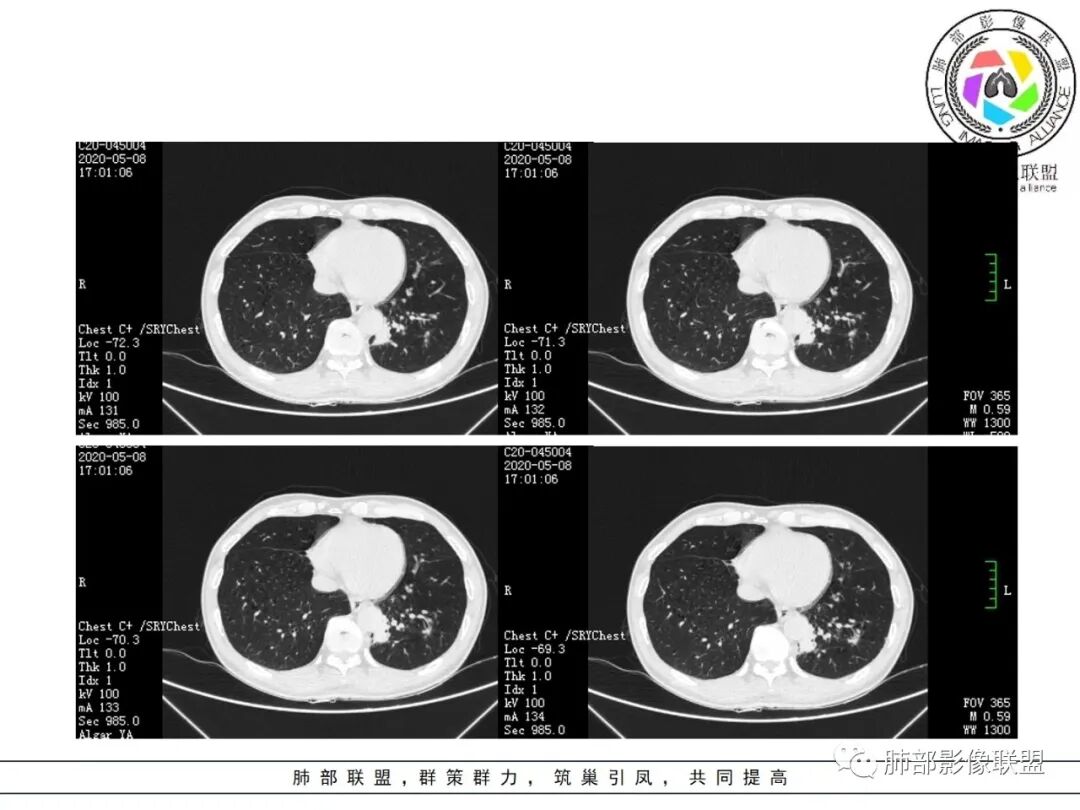

1.关于病灶分布:本例多发小片影局限在左肺下叶,其他肺叶未见异常病灶。

而肺结核表现为多灶性、多形态、多钙化性,本例前述征象均未见到,亦未见结核的典型树芽征。故肺结核缺乏支持点。

2.关于支气管:上述病灶辖区外侧段支气管截断,环壁结节,远端阻塞性肺炎,是肺癌的重要征象。